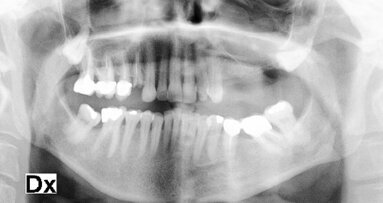

Nel caso raffigurato il paziente portatore di una protesi scheletrata nell’arcata superiore chiede una riabilitazione fissa del mascellare superiore (Figg. 1-5).

La pneumatizzazione dei seni mascellari ha ridotto notevolmente l’altezza ossea in posizione dei primi molari, tale da non permettere l’inserimento degli impianti se non con una terapia rigenerativa (Figg. 6, 7).

L’anamnesi positiva per una sinusite cronica e un’abitudine viziata di forte fumatore ha escluso l’intervento di elevazione della membrana sinusale.